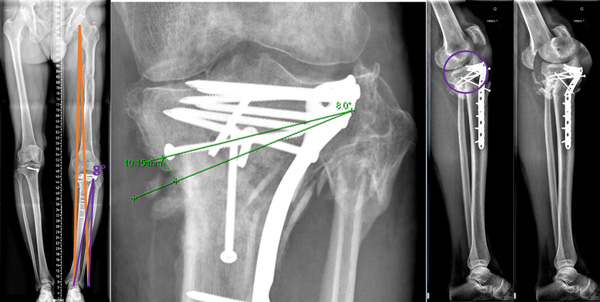

8 Months xrays

Knee stable but stiff walk without crusches

8 Months xrays Knee stable but stiff walk without crusches

Pre-operative planning

Aimed for slight varus (symetric)